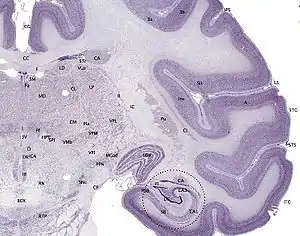

Hippocampus

The hippocampus provides animals with a spatial map of their environment.[30] It stores information regarding non-egocentric space (egocentric means in reference to one's body position in space) and therefore supports viewpoint independence in spatial memory.[31] This means that it allows for viewpoint manipulation from memory. It is important for long-term spatial memory of allocentric space (reference to external cues in space).[32] Maintenance and retrieval of memories are thus relational or context dependent.[33] The hippocampus makes use of reference and working memory and has the important role of processing information about spatial locations.[34]

Blocking plasticity in this region results in problems in goal-directed navigation and impairs the ability to remember precise locations.[35] Amnesic patients with damage to the hippocampus cannot learn or remember spatial layouts, and patients having undergone hippocampal removal are severely impaired in spatial navigation.[31][36]

Monkeys with lesions to this area cannot learn object-place associations and rats also display spatial deficits by not reacting to spatial change.[31][37] In addition, rats with hippocampal lesions were shown to have temporally ungraded (time-independent) retrograde amnesia that is resistant to recognition of a learned platform task only when the entire hippocampus is lesioned, but not when it is partially lesioned.[38] Deficits in spatial memory are also found in spatial discrimination tasks.[36]

Large differences in spatial impairment are found among the dorsal and ventral hippocampus. Lesions to the ventral hippocampus have no effect on spatial memory, while the dorsal hippocampus is required for retrieval, processing short-term memory and transferring memory from the short term to longer delay periods.[39][40][41] Infusion of amphetamine into the dorsal hippocampus has also been shown to enhance memory for spatial locations learned previously.[42] These findings indicate that there is a functional dissociation between the dorsal and ventral hippocampus.

Hemispheric differences within the hippocampus are also observed. A study on London taxi drivers, asked drivers to recall complex routes around the city as well as famous landmarks for which the drivers had no knowledge of their spatial location. This resulted in an activation of the right hippocampus solely during recall of the complex routes which indicates that the right hippocampus is used for navigation in large scale spatial environments.[43]

The hippocampus is known to contain two separate memory circuits. One circuit is used for recollection-based place recognition memory and includes the entorhinal-CA1 system,[44] while the other system, consisting of the hippocampus trisynaptic loop (entohinal-dentate-CA3-CA1) is used for place recall memory[45] and facilitation of plasticity at the entorhinal-dentate synapse in mice is sufficient to enhance place recall.[46]

Place cells are also found in the hippocampus.